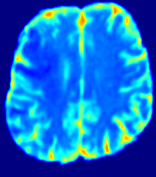

For a better insight into an estimated velocity field 𝐕𝐕{\bf{V}} and diffusion field 𝐃𝐃{\bf{D}}, we compute the following maps: (1) 𝐕rgbsubscript𝐕𝑟𝑔𝑏{\bf{V}}_{rgb}: Color-coded orientation map of 𝐕=(Vx,Vy,Vz)T𝐕superscriptsuperscript𝑉𝑥superscript𝑉𝑦superscript𝑉𝑧𝑇{\bf{V}}=(V^{x},V^{y},V^{z})^{T}, obtained by normalizing 𝐕𝐕{\bf{V}} to unit length and mapping its 3 components to red, green, blue respectively; (2) 𝐕2subscriptnorm𝐕2\|{\bf{V}}\|_{2}: 222 norm of 𝐕𝐕{\bf{V}}; (3) D𝐷D: scalar field in Eq. 5.

Fig. 3 and Fig. 4 show the PIANO feature maps estimated from two ISLES 2017 patients: all are highly consistent with the lesion in both cases. Details of the blood flow trajectories are revealed in 𝐕rgbsubscript𝐕𝑟𝑔𝑏{\bf{V}}_{rgb} by the ridged patterns and the sharp changes of colors in the unaffected (right) hemisphere, while the flat patterns appearing within the lesion provide little directional information about the velocity and indicate low velocity magnitudes. Velocity magnitudes are more directly visualized via 𝐕2subscriptnorm𝐕2\|{\bf{V}}\|_{2}, from which one can easily locate the lesion where 𝐕2subscriptnorm𝐕2\|{\bf{V}}\|_{2} is low. D𝐷D also indicates lower diffusion values in the lesion, though with less contrast potentially due to the fact that it captures the accumulated effect of CA diffusion at the voxel-level.

Fig. 7 compares the PIANO and ISLES 2017 maps based on the above three metrics computed from 43 patients, where μrsuperscript𝜇𝑟\mu^{r} of 𝐕2subscriptnorm𝐕2\|{\bf{V}}\|_{2} achieves the lowest value, meaning more significant differences between lesion and c-lesion. Moreover, Fig. 7 (b) shows 𝐕2subscriptnorm𝐕2\|{\bf{V}}\|_{2} reveals much stronger differences between a lesion and its c-lesion compared to all other maps. Tab. 1 summarizes results over all patients. The most distinguishing results are obtained from PIANO feature maps.